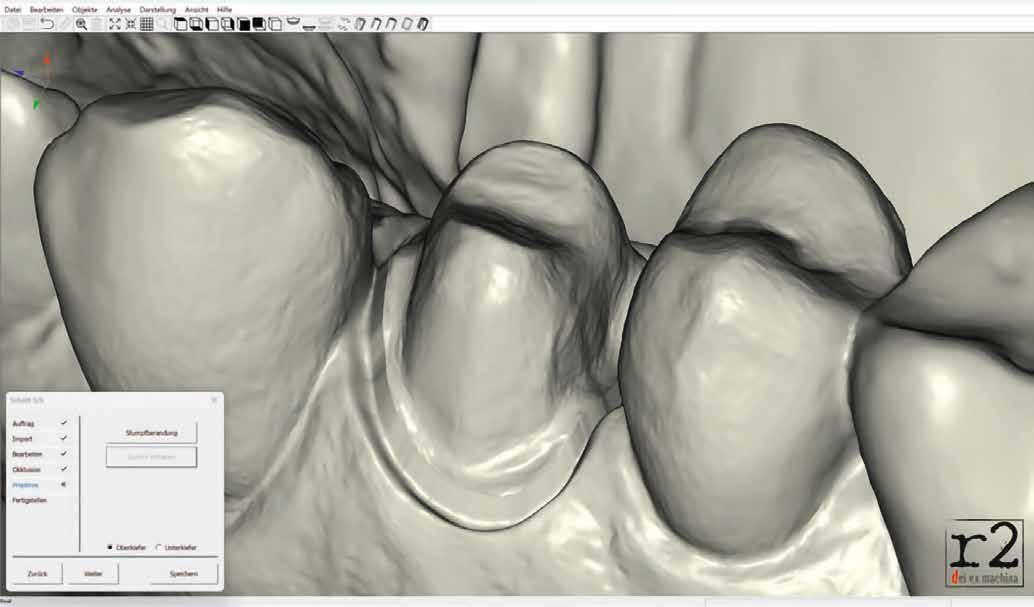

építményhez gyári Camlog titánbázist használtunk, amit előzetesen befedtünk DCMhotbond fusio connect spray-vel. A titánbázis felületi kondicionálásához alkalmazott anyag kiváló, résmentes és tartós kötési alapot teremt a bázis és a rá készülő cirkon konstrukció között1. A cirkónium-dioxid egyedi felépítmény tervezését primer teleszkóp koronaként választottuk ki a CAD-szoftveres lehetőségek tárából. A felső mintát a beszórt titánbázissal ínymaszkkal és anélkül is beszkenneltük, akárcsak az antagonista mintát. A titánbázist hárompontos vonatkoztatással illesztettük a digitális mintába, majd megállapítottuk a behelyezési irányt és az illesztő paramétereket (7–13. képek).

Digitális tervezés

A mintát beolvastuk (D1000, 3Shape), majd megterveztük a munkát (3Shape Dental System) (6. kép). A fel -